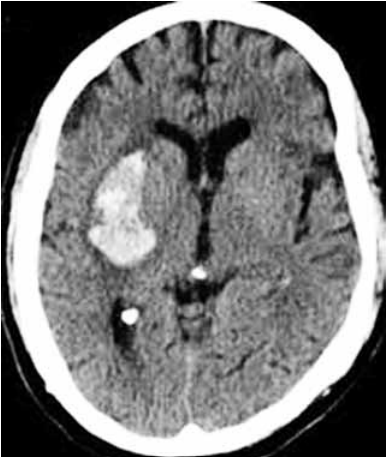

Paciente do sexo masculino, 58 anos, hipertenso prévio sem controle adequado e tabagista. Admitido com queixa de cefaleia e hemiplegia completa à esquerda de início súbito há 4 horas da admissão hospitalar. No momento apresenta pontuação na escala do NIH de 12, pressão arterial de 210/100 mmHg, FC: 87 bpm, ritmo sinusal no monitor cardíaco. Tomografia de crânio a seguir.

(https://www.google.com/imgres?)

Assinale a alternativa correta referente ao tratamento na fase aguda desse paciente.